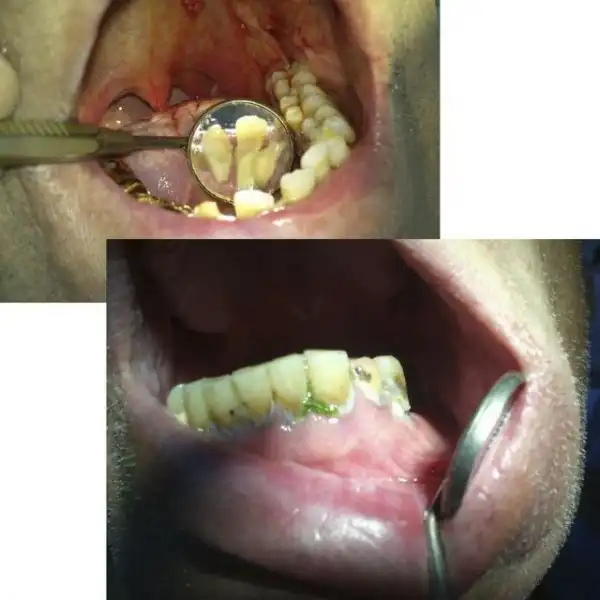

Угадайте, а сколько лет этому пациенту? По понятным причинам я не фотографировал его лицо полностью… Изначально он обращался около двух месяцев назад с переломом нижней челюсти в области суставного отростка слева, и шины наложить ему не могли, т.к. зубов целых почти нет… Был направлен в областную больницу, где походил с пращевидной бинтовой повязкой, и был отпущен домой… Остеосинтеза никто ему не делал. А потом спустя месяца два попал ко мне, после того как у себя на работе упал и ударился тем же местом)))) Очень «правдоподобно»… Но не в этом суть, парню 25 лет!!! Считает, что зубы разрушены, т.к. он на вредном производстве на заводе работает. Но гораздо более вероятная причина — нежелание чистить зубы. На фотографии видно, сколько там налета. И так многие выдумывают самые невероятные причины: работа с кислотой, жизнь в тайге, дальние плаванья, утрата зубов за один месяц после родов и т.п. Все это может повлиять в какой-то степени, но на деле у всех этих пациентов ужасная гигиена и последнее посещение стоматолога при царе Грохе. А у нашего парня зато татуха на всю правую руку, и на то, чтоб ее сделать, он нашел и время, и деньги, и желание… Это наш менталитет… Ездить на дорогой машине, понаделать татух, пирсинг, ходить в дорогих шмотках, но при этом с грязными ушами и нечищеными зубами. Редко кто на приеме попадается с таким уровнем гигиены, чтоб можно было стоматологическое вмешательство проводить. Да-да, есть индекс гигиены специальный, и если он выше определенной величины, то удалять нельзя. Но на деле удаляю, т.к. если строго подходить, то принять можно будет 2-3 человек за смену, остальных отправлять чистить зубы… Но потом люди приходят и с удивлением спрашивают, почему лунка после удаления болит? Никому даже в голову не приходит, что одной из вероятных причин может быть помойка во рту… Так что, друзья, идете к стоматологу — почистите зубы хорошенько ( да и вообще их чистить надо)), даже этой мелочью вы обеспечите себе хорошее отношение врача, потому что чистый рот — большая редкость и приятная неожиданность для стоматолога( к сожалению).

Еще пару слов о гигиене… Вот два типичных пациента. У одного укроп на зубах, у второго камни (видны в зеркале). И это не самые яркие примеры. Представьте, что после удаления попадает в кровоточащую лунку… Меня вообще трудно удивить или вызвать отвращение, но некоторым удается. Иногда просто отправляю из кресла идти чистить зубы. Где? Меня не касается… Так обижаются!!! Тонкие натуры) Был случай, как одного такого запущенного принял, удалил зуб, но предупредил, что если еще раз с таким ртом придет, то я его не приму. Он пришел- картина та же. я ему в приеме отказал. Это первая смена была. А вечером зашел в кабинет зачем-то, там мой коллега прием вел, смотрю -сидит у него в кресле мой утренний пациент. Спрашиваю доктора, почистил ли тот мужик зубы, а он мне говорит, что такой помойки он не видел еще, как у него во рту… Занавес…